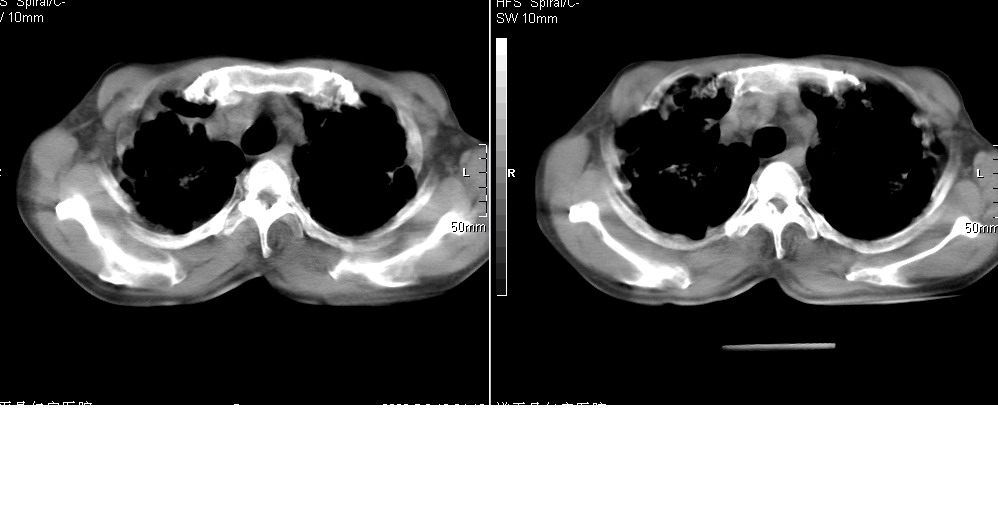

以下是引用光线在2008-5-6 18:36:00的发言:[br]双肺结核(左上肺空洞形成)、间质性改变合并感染,右肺大泡;右侧胸膜增厚。

以下是引用zsl6918在2008-5-7 1:54:00的发言:[br]首先肺泡蛋白质沉着症,其次考虑机遇性感染。